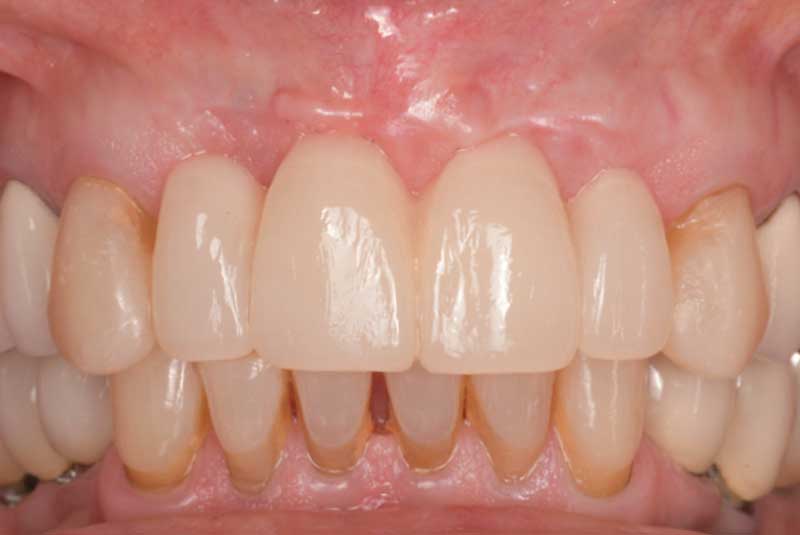

Before & After Veneers (#6,8,9,10,11,12) Crowns (23,24,25,26) Bridge (#27-28p-29), Overlay #21, Implant & Implant Crowns (#7,13,14,15,18,19,20,22), Composite (#3,4,5,12)